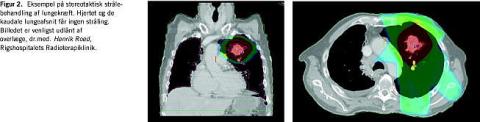

Teknikken er lovende, da den er virksom til lokalkontrol af mindre lungeinfiltrater, og toksiciteten er begrænset. I Figur 2 vises et eksempel på fordelingen af stråledosis mellem tumor og omgivende normalt væv i forbindelse med stereotaktisk strålebehandling af en lungetumor. På Rigshospitalet er metoden implementeret til en nøje afgrænset patientgruppe. Onkologisk Afdeling, Århus Universitetshospital, indgår i en skandinavisk undersøgelse til nærmere karakterisering af teknikkens værdi ved behandling af lungekræftpatienter.